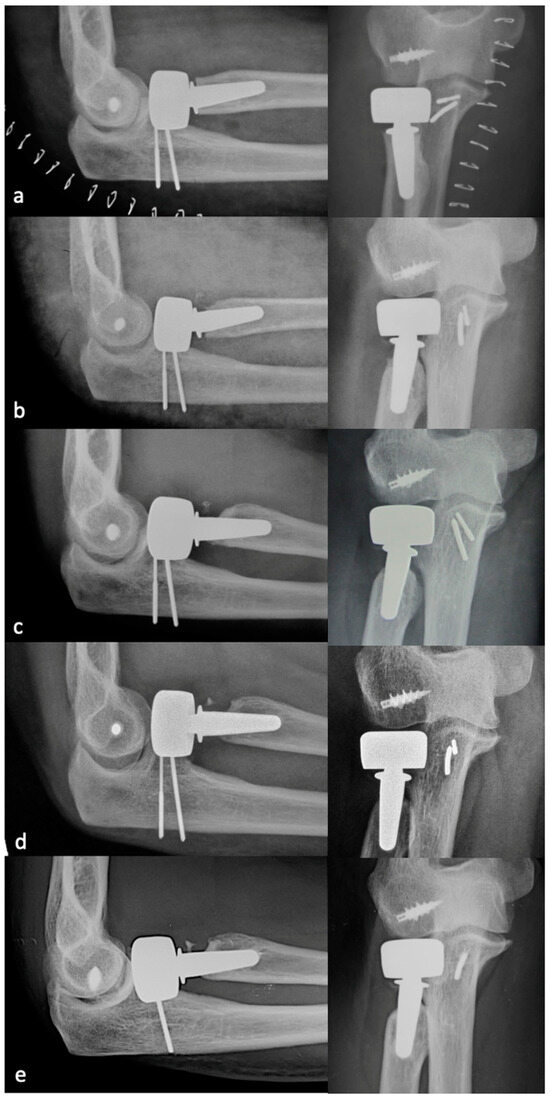

PRNR was mild in 27 patients (33%), who had an mPRNR of 1.9 mm (range: 0–2.9); PRNR was moderate in 44 patients (54%), who had an mPRNR of 4.5 mm (range: 3.1–5.9); lastly, PRNR was severe in 11 patients (13%), who had an mPRNR of 7 mm (range: 6–9.4). The typical progression of PRNR over time for an anatomical RHA is shown in Figure 3, while that for a bipolar implant is shown in Figure 4. Table 1 shows the clinical result scores in the subgroups stratified according to PRNR severity. No significant differences were observed in either the clinical characteristics or the clinical scores between the three subgroups. Indeed, no significant correlations (p = 1) (Table 2) were detected between the degree of PRNR and any of the clinical parameters in each subgroup.

Figure 3.

Progression of PRNR over time in an anatomical press-fit RHA. X-rays performed postoperatively at 2 weeks (a), 6 months (b), 1 year (c), 2 years (d), and 7 years (e). PRNR progressed until the end of the second year, while no further progression was observed beyond 2 years.

Figure 4.

Progression of PRNR over time in a bipolar press-fit RHA. X-rays performed postoperatively at 2 weeks (a), 6 months (b), 1 year (c), 2 years (d), and 9 years (e). PRNR progressed until the end of the second year, while no further progression was observed beyond 2 years.